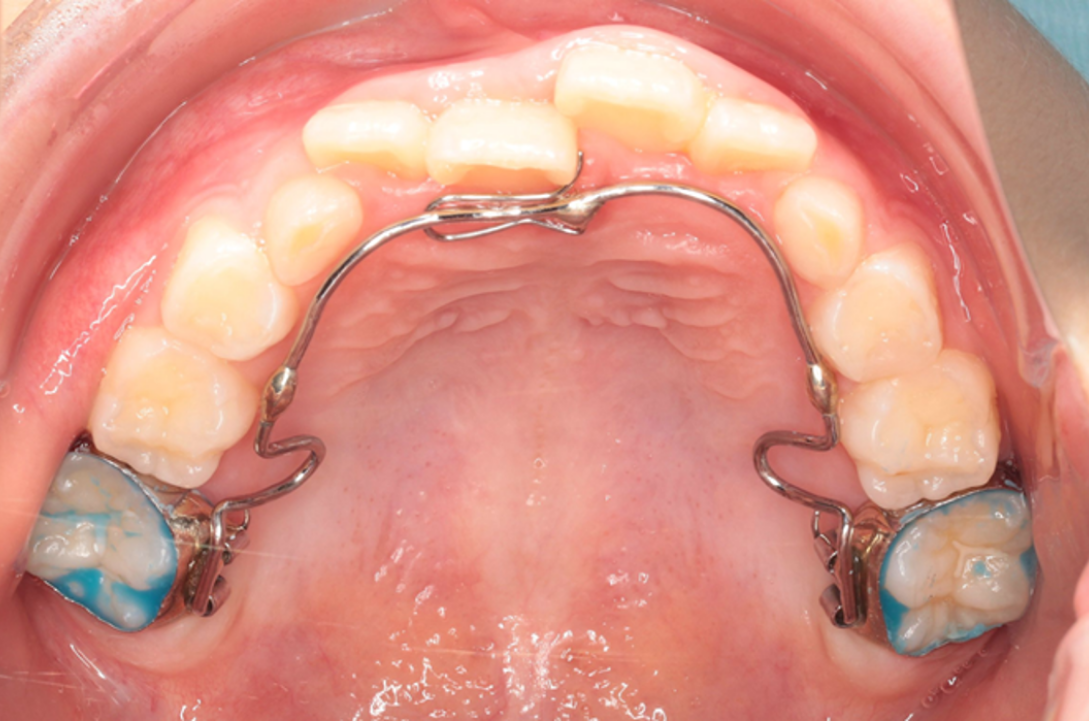

交差している歯並びを改善しました

Under Treatment